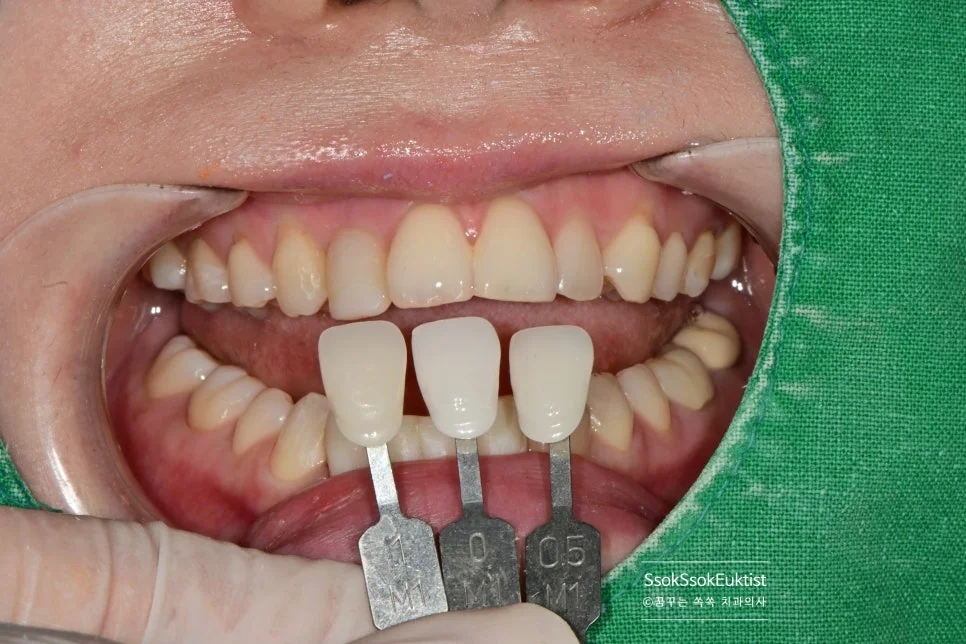

가장 어울리는 색상을 찾기 위해 Shade-guide를 적용하여 최대한 많은 정보를 기공실에 전달합니다^^ 그렇게 하여 아래 앞니 4개의 크라운을 제작해 보았습니다.